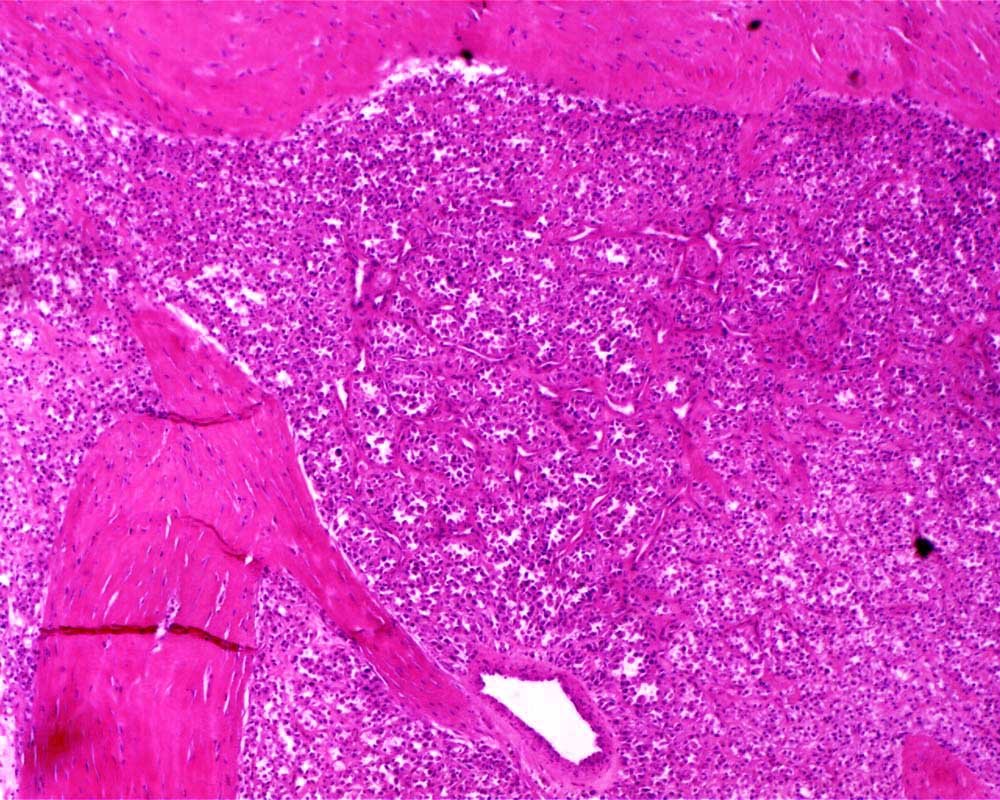

Case: ThighMass

Final Diagnosis: